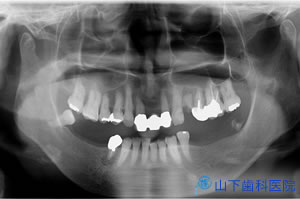

| 5年経過後のレントゲン写真です。 | ![]() |